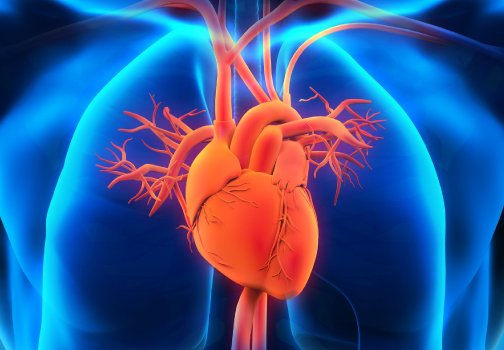

Cardilogy is a field which includes medical diagnosis and treatment of congenital heart defects, coronary artery disease, heart failure, valvular heart disease and electrophysiology. Physicians who specialize in this field of medicine are called cardiologists, a specialty of internal medicine.